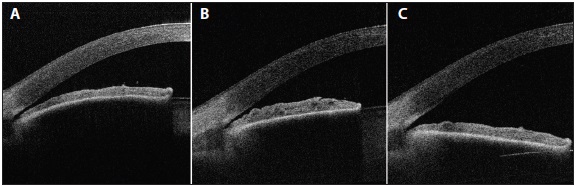

As the crystalline lens ages and becomes cataractous, it thickens and may secondarily narrow the anterior chamber angle.7 Numerous studies over the past decade have shown that lens extraction with IOL implantation is also a reasonable option for the management of PAC and PACG, maybe even more effective than LPI.8 Anatomical studies using anterior segment optical coherence tomography imaging have demonstrated that the angle deepens more after lens extraction than after LPI (Figure).9

Figure. Anterior segment optical coherence tomography of an eye before treatment (A), 1 week after LPI (B), and 1 week after lens extraction (performed 4 months after LPI; C).